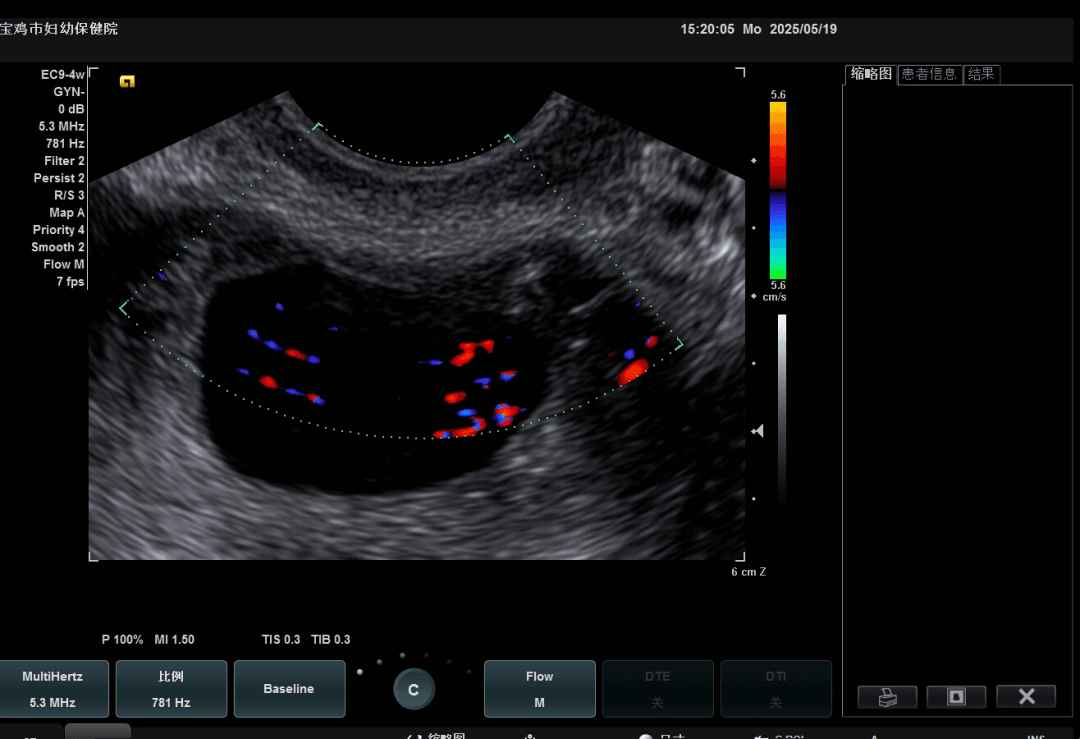

治疗后血流阻断

经专家综合评估并与患者沟通后,决定为其实施超声引导下瘢痕部妊娠聚桂醇硬化治疗。治疗后,病灶周边血流完全阻断,清宫术中出血量明显减少,术后3周血HCG恢复正常,月经周期也恢复良好。